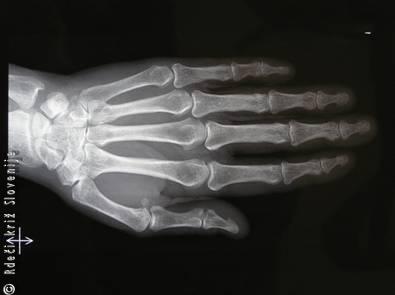

Slika 17

Rentgenska slika skeleta roke.